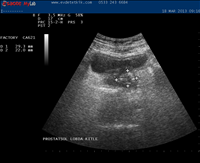

Hizmetimizden görüntüler